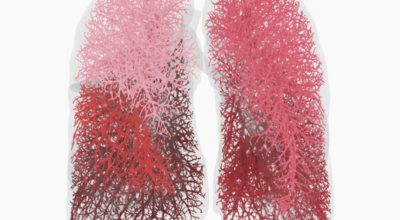

폐렴은 폐의 실질 조직에 염증이 생기는 질환으로, 주로 세균, 바이러스, 곰팡이 등의 감염에 의해 발생합니다. 폐렴은 감염성 질환이므로 전염될 수 있으며, 특히 면역력이 약한 영유아, 노인, 만성 질환자에게 더욱 위험합니다. 폐렴은 발생 위치에 따라 대엽성 폐렴과 기관지 폐렴으로 나뉘며, 원인균에 따라 세균성 폐렴, 바이러스성 폐렴, 곰팡이성 폐렴 등으로 분류됩니다.